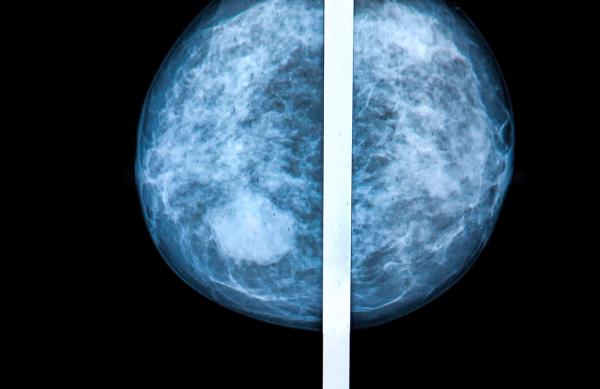

"Unfortunately, for years and years they didn't do it. They would simply say that there's nothing showing up on the mammogram, which means you could have extremely dense breasts — very high risk of cancer — and the mammography report would simply say, 'We don't see any cancer,' which is a horrible misuse of these technologies," Dr. Bard, a leader in the field of radiology, says.

Women whose breasts have been identified as being highly dense are now notified [at least in 27 states] of the findings, though other methods of visualizing breast tissue [sonography, MRI] are not discussed routinely enough.